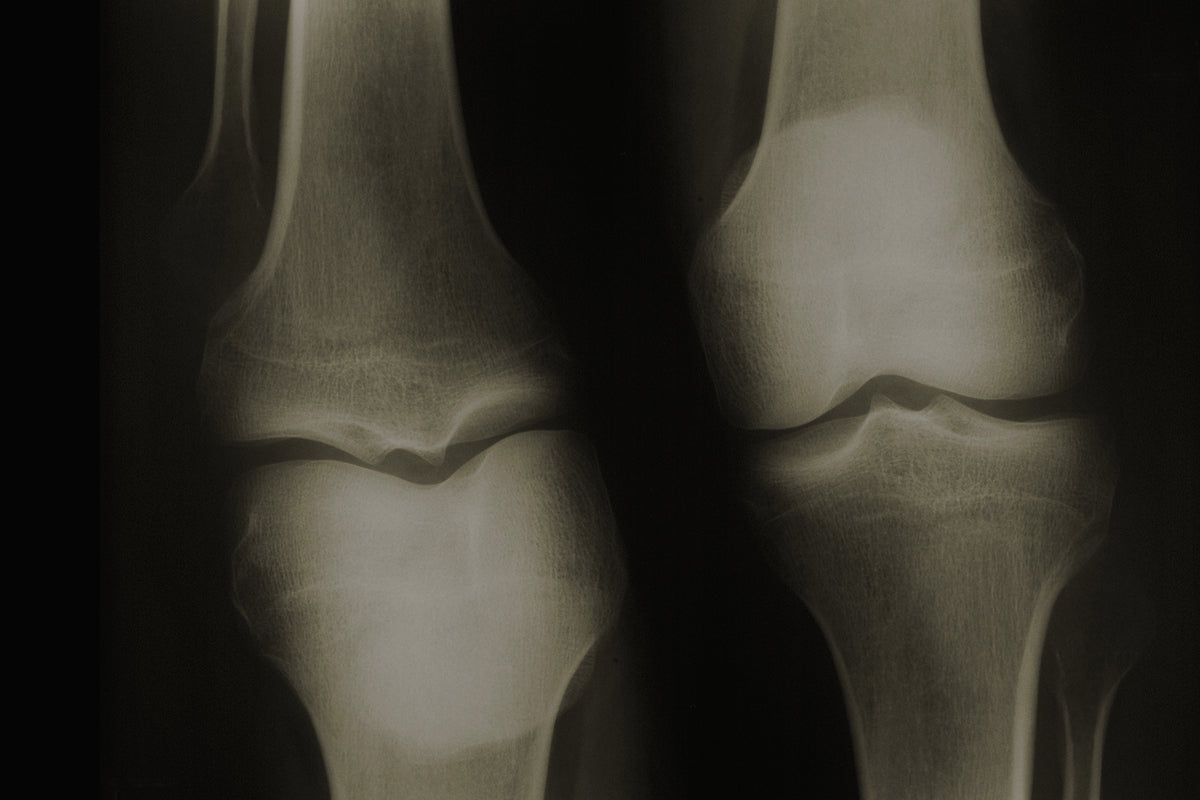

El dolor en las articulaciones es una molestia muy habitual, no solo para personas mayores, sino también para deportistas, personas con trabajos físicos exigentes o que padecen enfermedades como la artritis o la artrosis. La rigidez al despertar, la pérdida de movilidad o la inflamación crónica pueden convertirse en una carga constante que afecta significativamente a la calidad de vida.

La inflamación en los huesos y articulaciones es una respuesta del sistema inmunológico ante lesiones, desgaste, estrés oxidativo o enfermedades autoinmunes como la artritis. Cuando esta respuesta se mantiene en el tiempo, se produce un daño progresivo en los cartílagos, ligamentos y tejidos conectivos.